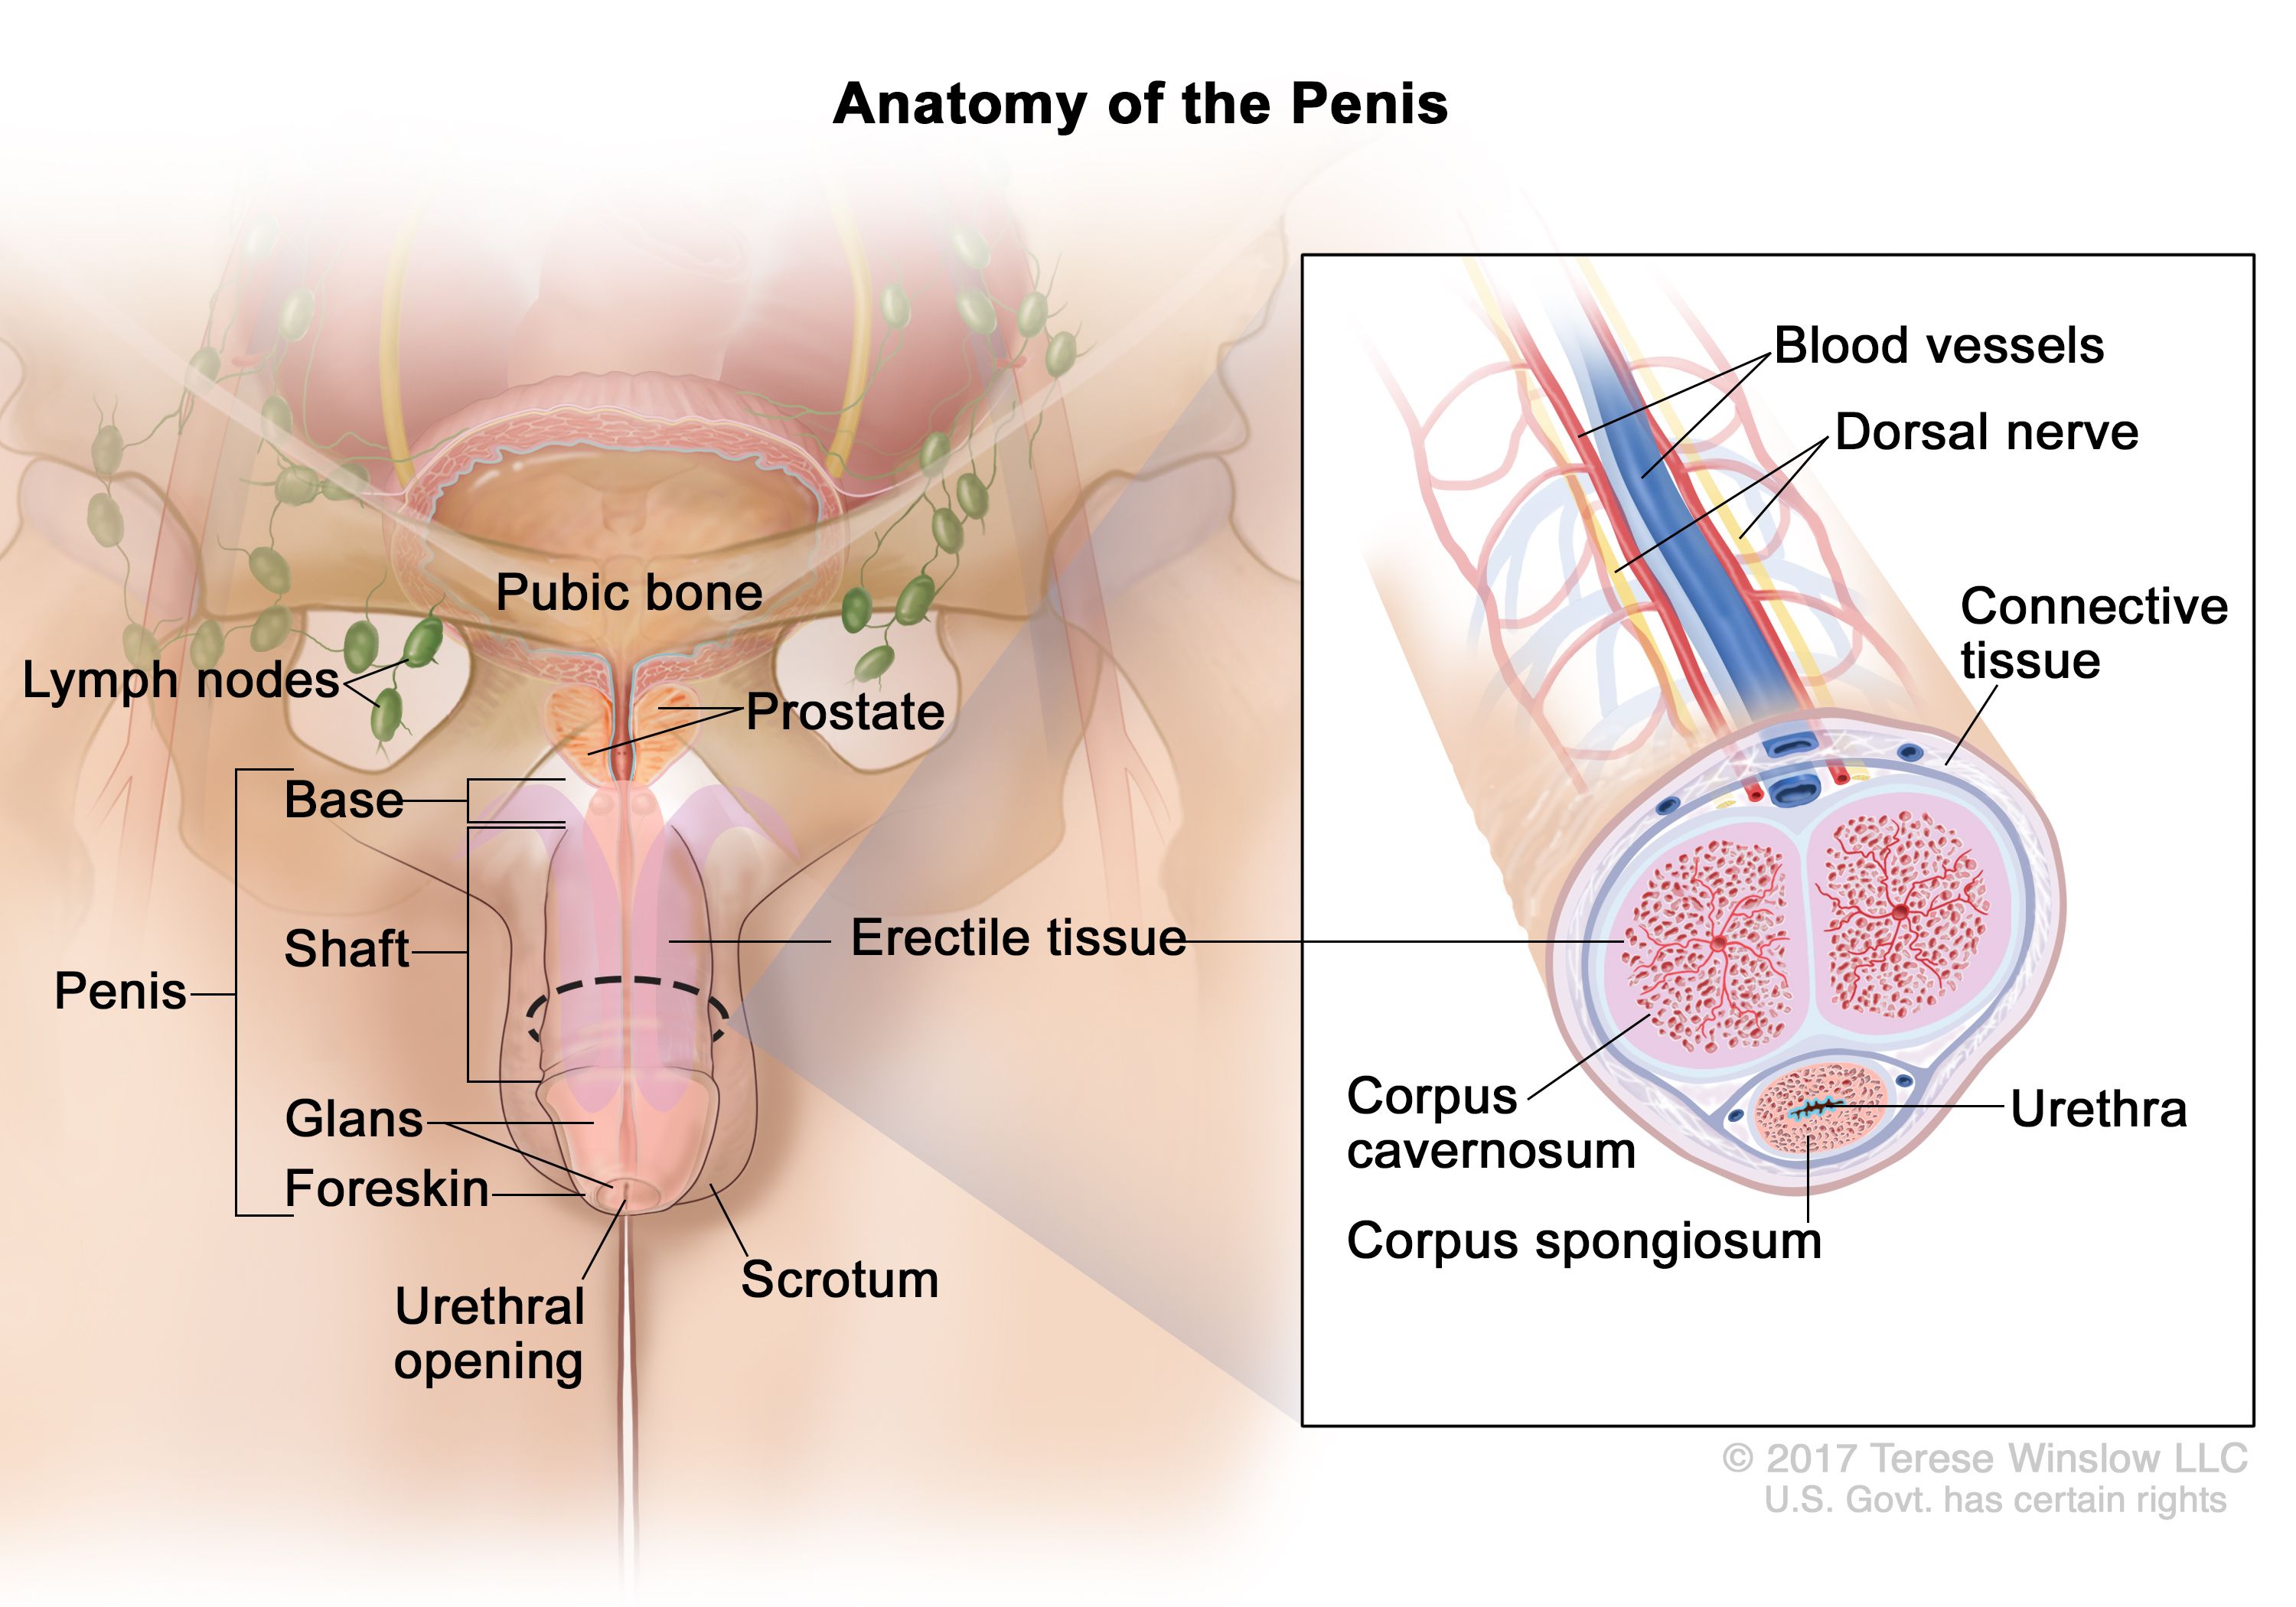

Definition of corpus spongiosum NCI Dictionary of Cancer Terms NCI on sale, Corpus spongiosum penis Wikipedia on sale, Corpus spongiosum penis anatomy Britannica on sale, Corpus cavernosum penis Wikipedia on sale, Corpus Spongiosum of Penis Right Half Complete Anatomy on sale, Corpus spongiosum penis anatomy Britannica on sale, What is the Difference Between Corpus Cavernosum and Corpus on sale, Anatomy corpora cavernosa and spongiosum note the rather large on sale, Corpus Spongiosum StoryMD on sale, Corpus spongiosum penis Wikipedia on sale, Penis Brandywine Urology Consultants on sale, The Penis Structure Muscles Innervation TeachMeAnatomy on sale, SEER Training Penis on sale, Corpus Spongiosum of Penis Left Half Complete Anatomy on sale, Corpus spongiosum penis on sale, Corpus spongiosum Location Functions and Pictures Bodterms on sale, Corpus spongiosum of penis e Anatomy IMAIOS on sale, 3d rendered medically accurate illustration of the corpus on sale, Corpus Spongiosum of Penis Left Half Complete Anatomy on sale, Corpus Spongiosum 6 by Sebastian Kaulitzki science Photo Library on sale, How to identify priapism Medmastery on sale, Penis Anatomy Histology Histology Flashcards ditki medical on sale, Penis Radiology Reference Article Radiopaedia on sale, Corpus spongiosum Location Function Problems and Pictures on sale, Corpus spongiosum hi res stock photography and images Alamy on sale, Hypothesis that urethral bulb corpus spongiosum plays an active on sale, Corpus spongiosum is a part ofA. OvaryB. TestisC. UterusD. Male on sale, Normal penile anatomy. a Drawing axial view illustrates the on sale, 64 Corpus Spongiosum Royalty Free Photos and Stock Images on sale, Symptomatic corpus spongiosum defect in adolescents and young on sale, Corpus Spongiosum 10 by Sebastian Kaulitzki science Photo Library on sale, Corpus Spongiosum Penis Anatomy Function Diagram Body Maps on sale, urethra and corpus spongiosum Histologia on sale, Corpus cavernosum penis Wikipedia on sale, Tissue 177 Penile Urethra and Corpus Spongiosum on sale.

Definition of corpus spongiosum NCI Dictionary of Cancer Terms NCI on sale, Corpus spongiosum penis Wikipedia on sale, Corpus spongiosum penis anatomy Britannica on sale, Corpus cavernosum penis Wikipedia on sale, Corpus Spongiosum of Penis Right Half Complete Anatomy on sale, Corpus spongiosum penis anatomy Britannica on sale, What is the Difference Between Corpus Cavernosum and Corpus on sale, Anatomy corpora cavernosa and spongiosum note the rather large on sale, Corpus Spongiosum StoryMD on sale, Corpus spongiosum penis Wikipedia on sale, Penis Brandywine Urology Consultants on sale, The Penis Structure Muscles Innervation TeachMeAnatomy on sale, SEER Training Penis on sale, Corpus Spongiosum of Penis Left Half Complete Anatomy on sale, Corpus spongiosum penis on sale, Corpus spongiosum Location Functions and Pictures Bodterms on sale, Corpus spongiosum of penis e Anatomy IMAIOS on sale, 3d rendered medically accurate illustration of the corpus on sale, Corpus Spongiosum of Penis Left Half Complete Anatomy on sale, Corpus Spongiosum 6 by Sebastian Kaulitzki science Photo Library on sale, How to identify priapism Medmastery on sale, Penis Anatomy Histology Histology Flashcards ditki medical on sale, Penis Radiology Reference Article Radiopaedia on sale, Corpus spongiosum Location Function Problems and Pictures on sale, Corpus spongiosum hi res stock photography and images Alamy on sale, Hypothesis that urethral bulb corpus spongiosum plays an active on sale, Corpus spongiosum is a part ofA. OvaryB. TestisC. UterusD. Male on sale, Normal penile anatomy. a Drawing axial view illustrates the on sale, 64 Corpus Spongiosum Royalty Free Photos and Stock Images on sale, Symptomatic corpus spongiosum defect in adolescents and young on sale, Corpus Spongiosum 10 by Sebastian Kaulitzki science Photo Library on sale, Corpus Spongiosum Penis Anatomy Function Diagram Body Maps on sale, urethra and corpus spongiosum Histologia on sale, Corpus cavernosum penis Wikipedia on sale, Tissue 177 Penile Urethra and Corpus Spongiosum on sale.